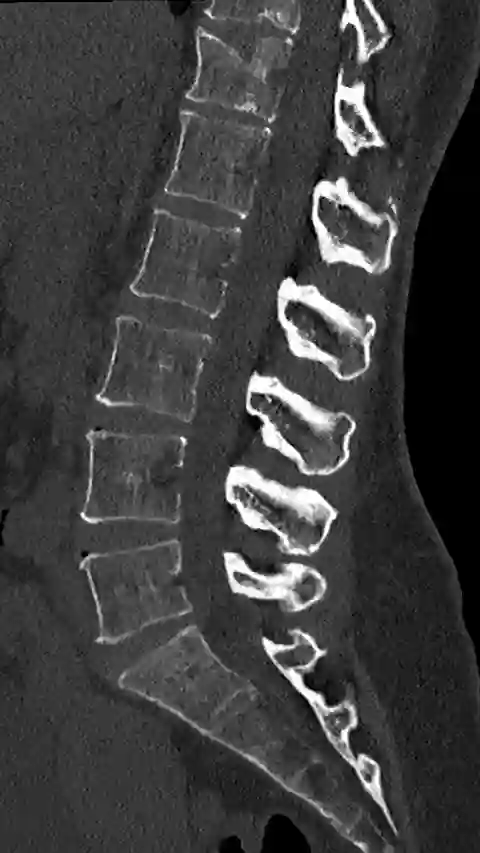

Sagittale CT-Bildgebung im Knochenfenster eines Patienten mit einem Morbus Baastrup.